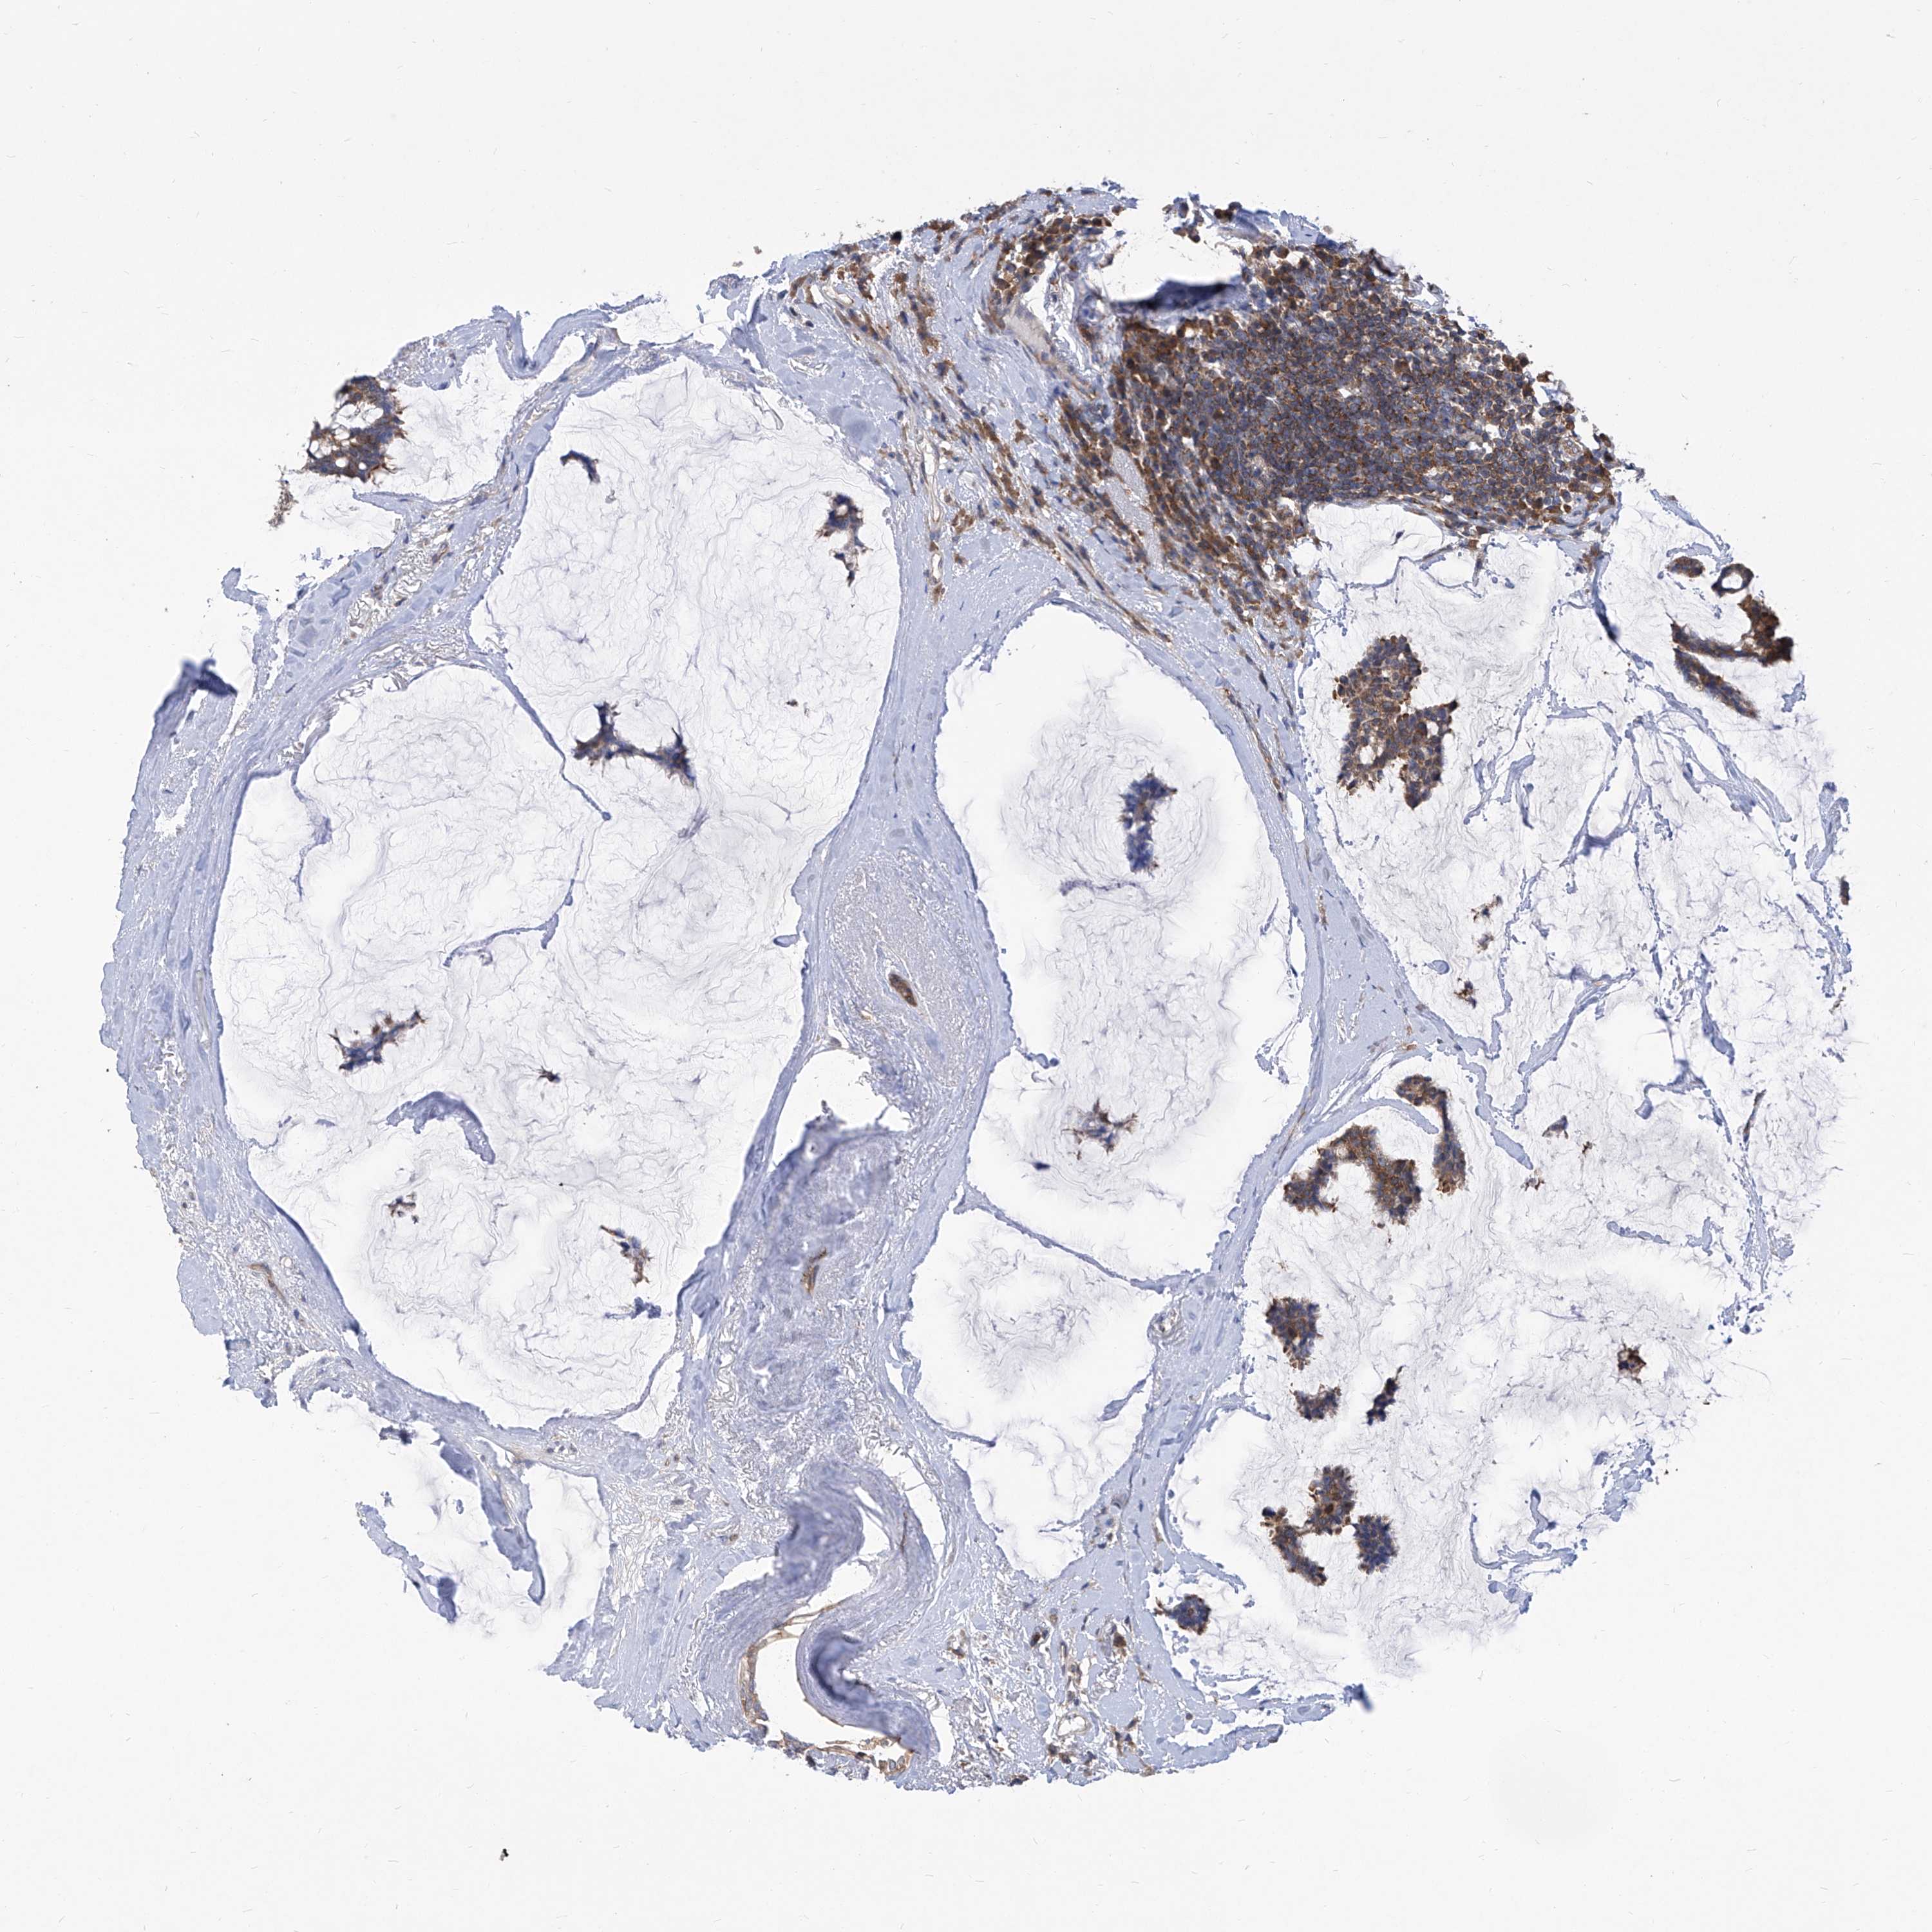

BRCA TCGA BRCA VALIDATION PROTEIN EXPRESSION